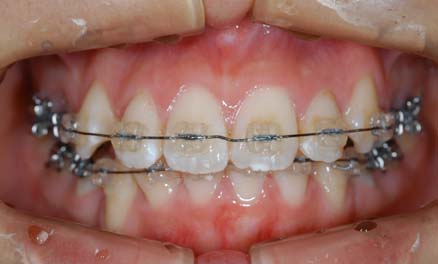

1.叢生(乱ぐい歯) 歯が重なり合ってでこぼこしています

治療前

上顎両側4番を抜歯

下顎両側4番も抜歯